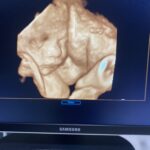

When is the best time for 3D/4D?

I think the best time for good 3D/4D images is anytime between 27 and 35 weeks. I have imaged some good ones as late as 37 weeks and as early as 21 weeks! However, it just all depends on multiple factors such as, position of the baby, placental location, umbilical cord location and fluid around the face.

Why are my ultrasound pictures and 3D images not as clear as my friend’s or the ones I see online?

There is a misconception when it comes to the perfect profile picture or the perfect 3D picture. The patient’s body habitus can play a big part. If you are overweight it can affect how clear the image is. This goes for 2D and 3D imaging. As far as 3D/4D images go, a lot has to line up just right. The baby needs to be in a good position, you need a good tech that has a lot of experience, there needs to be enough fluid around the face and if the placenta, the cord, or other body parts are covering the face, it can distort the image. I always try eveythig in my power to get the best images possible!